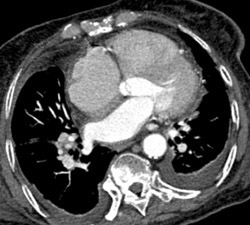

Calcified and Noncalcified Plaque in LAD